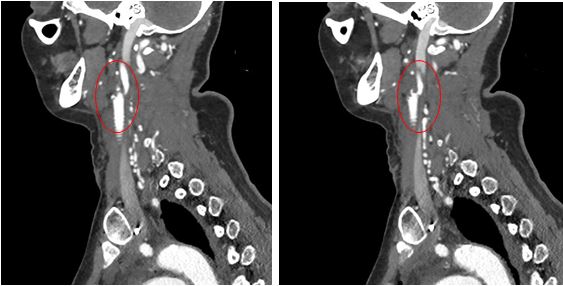

Gradually, the symptoms of the disease progressed, there was no constant monitoring, the patient did not receive treatment. She was examined again on an outpatient basis in 2019, occlusion of both CCAs was revealed (Figure 1). In the previous 6 months, she noted progression of cerebral symptoms in the form of unsteadiness of gait. There was also a tendency to arterial hypertension, antihypertensive therapy was selected at the place of residence, the target blood pressure level was achieved. DS of the brachiocephalic arteries (BCA) detected 90% stenosis of the left subclavian artery (SA), occlusion of the right SA. No lesions of the descending and abdominal aorta, of the visceral branches of the aorta, and of the arteries of the lower limbs were detected.

Fig. 1. Computed tomography of brachiocephalic arteries and the brain of the patient before surgical intervention (2020): cystogliotic alterations of the left frontal lobe (A); occlusion of the common carotid artery (B).